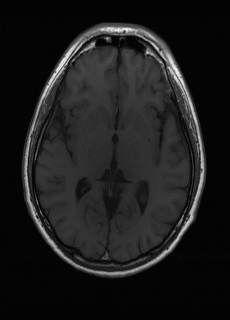

As we observe from the right image in Fig. 2, our BRM, both from MIMO and SISO settings, predicts the performance of dedicated models with a high correlation. We further choose the best three , and perform the last stage of fine-tuning accordingly to (6). A visual evaluation on real data is shown in Fig. 3. For simulated data, please refer to the Supplemental Material section.

Base on the best performing , we perceive that among , , and FLAIR, the results are best when is sampled the most. We suggest that this makes intuitive sense as images provide the best contrast out of the three sequences, which can compensate for the details lost in other images. The same observation can be made on the simulated data, where both and FLAIR show good contrast. When the time setting is changed to non-uniformity, we can see that our search for the best sampling strategy reflects the change. is sampled more as a result of faster acquisition time, while is still sufficiently sampled.

| Sequence | LR | SISO | MIMO | MIMO tuned | GT |

|---|---|---|---|---|---|

(a) 34.38/0.9371

(a) 34.38/0.9371

|

(b) 42.42/0.9883

(b) 42.42/0.9883

|

(c) 44.60/0.9920

(c) 44.60/0.9920

|

(d) 45.50/0.9940

(d) 45.50/0.9940

|

(e) PSNR/SSIM

(e) PSNR/SSIM

|

|

(f) 29.74/0.8903

(f) 29.74/0.8903

|

(g) 36.25/0.9734

(g) 36.25/0.9734

|

(h) 36.42/0.9752

(h) 36.42/0.9752

|

(i) 37.70/0.9832

(i) 37.70/0.9832

|

(j) PSNR/SSIM

(j) PSNR/SSIM

|

|

(k) 39.89/0.9311

(k) 39.89/0.9311

|

(l) 43.94/0.9864

(l) 43.94/0.9864

|

(m) 44.74/0.9883

(m) 44.74/0.9883

|

(n) 45.49/0.9894

(n) 45.49/0.9894

|

(o) PSNR/SSIM

(o) PSNR/SSIM

|